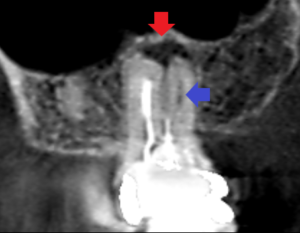

上顎大臼歯の近心頬側根の冠状断のCT画像です。

赤い矢印の先に膿の影がみられます。

青い矢印の先は、近心頬側根の2根管あるうちの未治療の方の根管です。

歯根の先まで石灰化しており、根管がCT画像でも確認出来ませんでした。